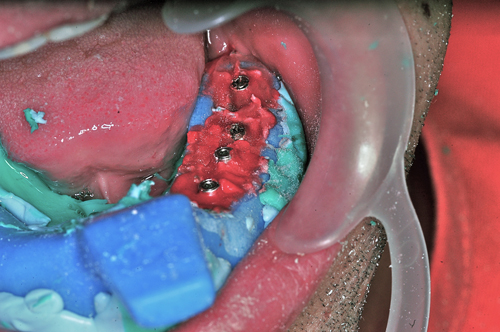

Palabras Clave: ELG: Estereolitográfico OH: Oclusión Habitual ORC: Oclusión en Relación Céntrica Paciente de 35 años de edad ,sexo masculino que lo derivan para implantar el tercer cuadrante. A la auscultación presenta ruidos articulares de tipo chasquido que remiten temporalmente luego de limitación de apertura bucal y maniobras quinesiológicas distractoras. También se observan recidivas de caries en algunos empastes y falta de disclusión canina de ambos lados. Se estudia el caso desde un punto de vista clínico, scanografico mediante Dentascan y tridimensional mediante montaje en articulador. A partir del scanner se obtienen datos para confeccionar modelo estereolitográfico (ELG),operar en el y construir férula quirúrgica dento-muco soportada. Habitualmente se procede directamente a implantar, dado que ese era el requerimiento del profesional derivante y el deseo del enfermo. Sin embargo, esa actitud enmascararía otro tipo de problemas que la boca presenta. Se consulta al odontólogo derivante, y coincide con mi opinión acerca de que si solo se lo implanta, sin corregir la posición mandibular, la situación de las ATMs, los empastes sin anatomía y la falta de disclusiones, el resultado final no será el deseado y su eficacia masticatoria no funcionará optimamente. Consultado el paciente coincide y acepta ese concepto y entonces procedemos a confeccionar un Jig de Lucia a partir del montaje de estudio, y lo dejamos puesto en boca toda la noche anterior a la consulta, para proceder a realizar un ajuste oclusal al día siguiente sin engramas anteriores, lo que facilita no tener que relajar nuevamente con laminillas de Long. En esta etapa pierde el implante correspondiente a la pieza 4.7 que traía en boca. Estabilizado el sistema, procedemos a la parte quirúrgica, comenzando por instalar la férula, retirar opérculos gingivales mediante bisturí circular, fresado óseo e instalación de implantes ,toma de impresión a cubeta fenestrada (pegando con metacrilato sin cambios dimensionales, los transfers a la cubeta especialmente diseñada.(1º método de pasividad protética utilizado), e instalación de tornillos de cicatrización. Inmediatamente de retirada la cubeta de boca y colocadas las réplicas de los implantes, procedemos a ferulizar los “ápices” de las réplicas para que no sufran movimientos durante el llenado de la impresión.(2º método de pasividad protética utilizado). Controlamos radiograficamente Tres meses después, procedemos a tomar nuevos registros de arco facial, registros intermaxilares en Oclusión en Relación céntrica, montaje de los modelos obtenidos intra operatoriamente y confección de un conjunto de cuatro coronas provisionales de metacrilato en el sector implantado y las correspondientes al maxilar superior. Verificada la perfecta función de todos los componentes, ausencia de todo tipo de síntoma y comprobada la paz en todo el sistema, procedemos tiempo después a confeccionar las fundas definitivas, que constituyen el “cerrojo” de la dinámica del mismo. Por último, corroboramos la oclusión fundamentalmente en lo que hace a la: